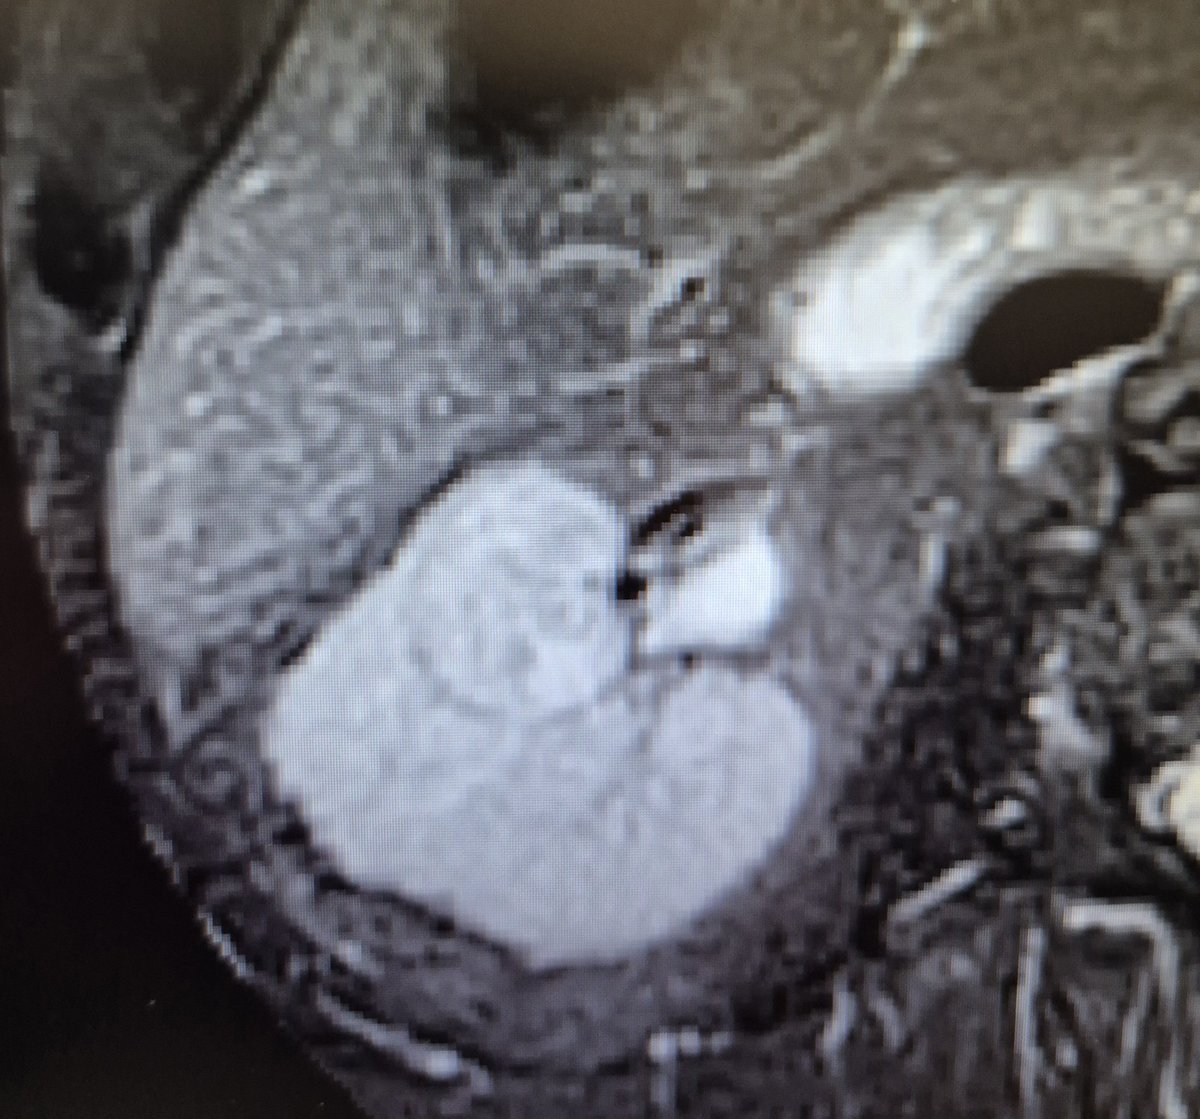

37

Curso de #nefrectomíaparcial robótica en #HURH Tumores sinusales endofiticos Un placer tener con nosotros a los Dres. Mario Martin y Leticia Polvorinos Gracias a @abexDaVinci por el apoyo ¡Orgulloso de mi equipo! @CoralManso

@ppalaciov

@kikegonzalez11

#RAPN

#training